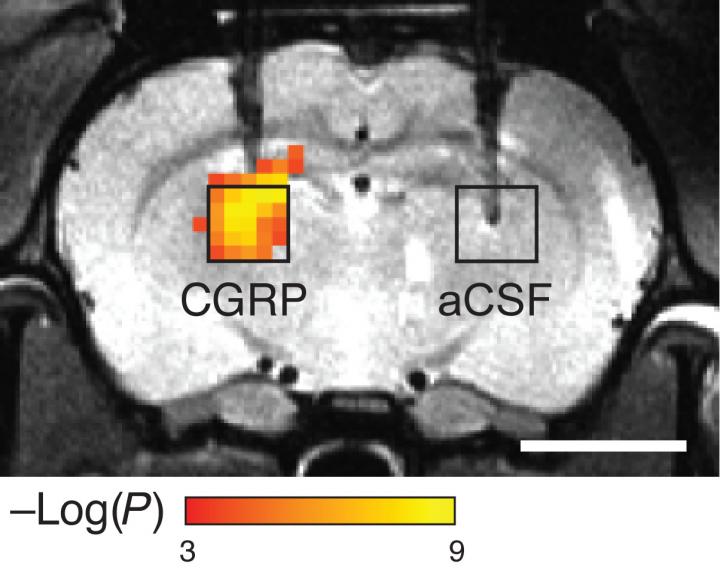

Indirect imaging

To make their probes, the researchers modified a naturally occurring peptide called calcitonin gene-related peptide (CGRP), which is active primarily during migraines or inflammation. The researchers engineered the peptides so that they are trapped within a protein cage that keeps them from interacting with blood vessels. When the peptides encounter proteases in the brain, the proteases cut the cages open and the CGRP causes nearby blood vessels to dilate. Imaging this dilation with MRI allows the researchers to determine where the proteases were detected.

"These are molecules that aren't visualized directly, but instead produce changes in the body that can then be visualized very effectively by imaging," Jasanoff says.